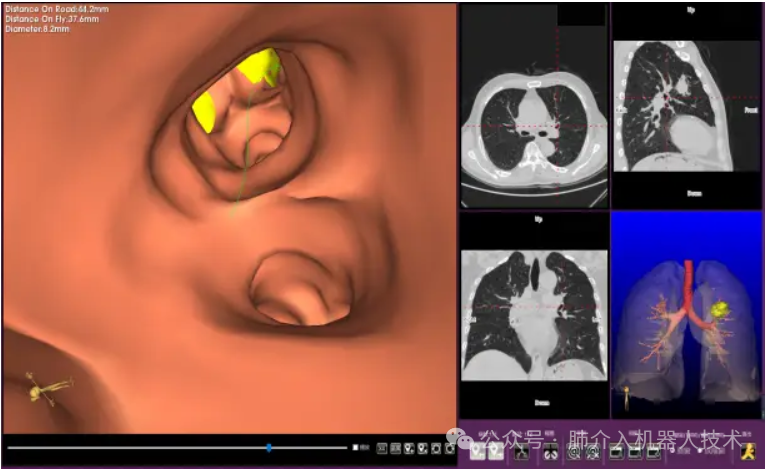

03、奧泰康助力肺部穿刺手術(shù)導航系統(tǒng)獲證

2024年1月31日,經(jīng)國家藥品監(jiān)督管理局公示,蘇州朗開醫(yī)療技術(shù)有限公司自主研發(fā)的肺部穿刺手術(shù)導航系統(tǒng)(國械注準20243010222)獲得NMPA批準上市,奧泰康助力本項目注冊申報服務(wù),系2024年奧泰康助力獲得的首張三類醫(yī)療器械注冊證。